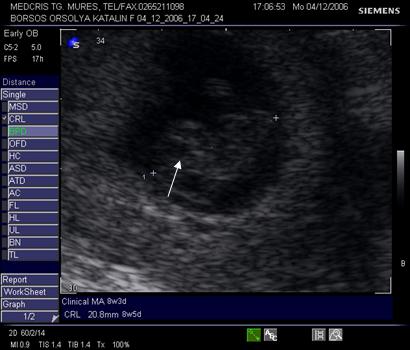

Fig nr. 12. Embrion corespunzator la 6 sapt si 3 zile

( masurat intre cele doua calipere )